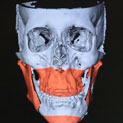

Paciente que cursa con prognatismo mandibular acompañado de maxilar superior plano; se observa la ausencia completa de proyección de los huesos malares, la tendencia a la esclera aparente y la incompetencia del labio superior.